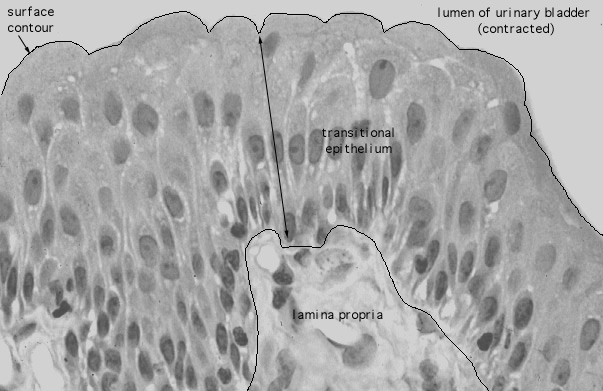

urinary bladder, transitional epithelium

165. Urinary System urinary bladder, transitional epithelium